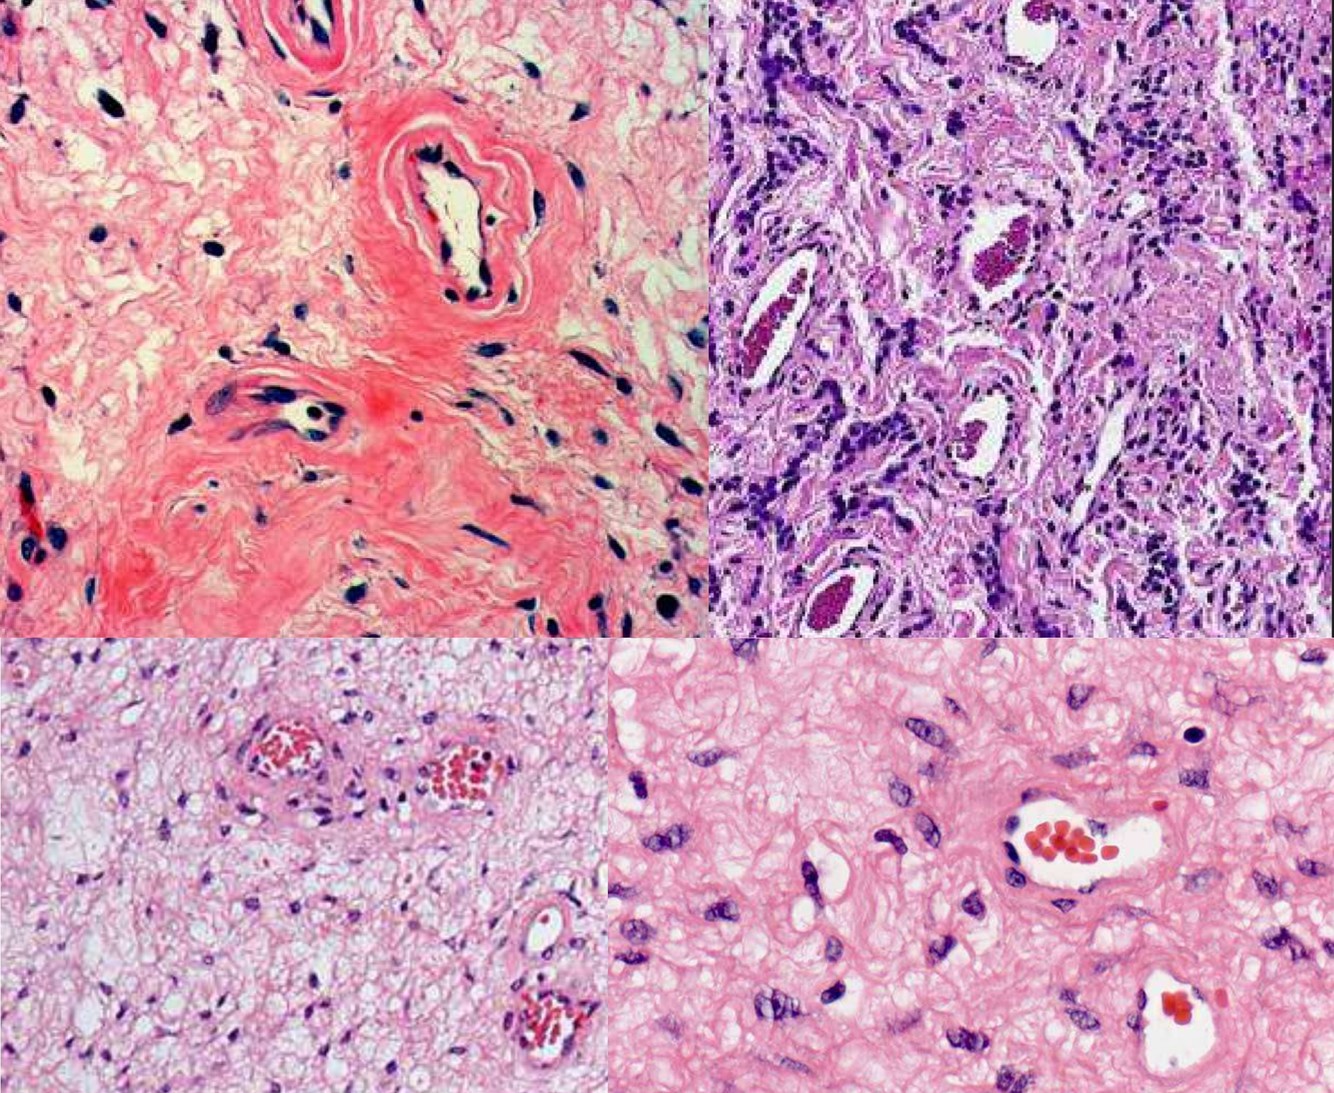

AGGRESSIVE ANGIOMYXOMA

Angiomyofibroblastoma